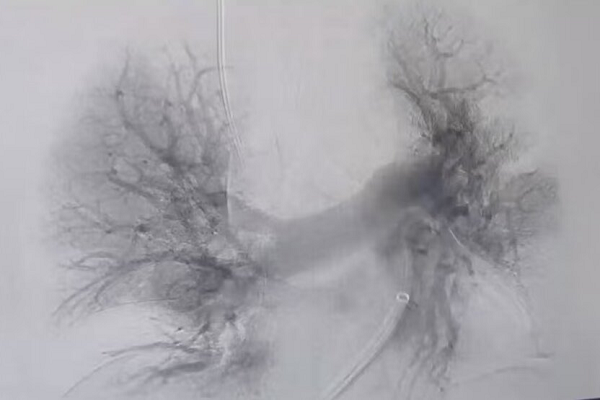

术中见左肺动脉主干未见显影,右肺动脉大分支多发充盈缺损